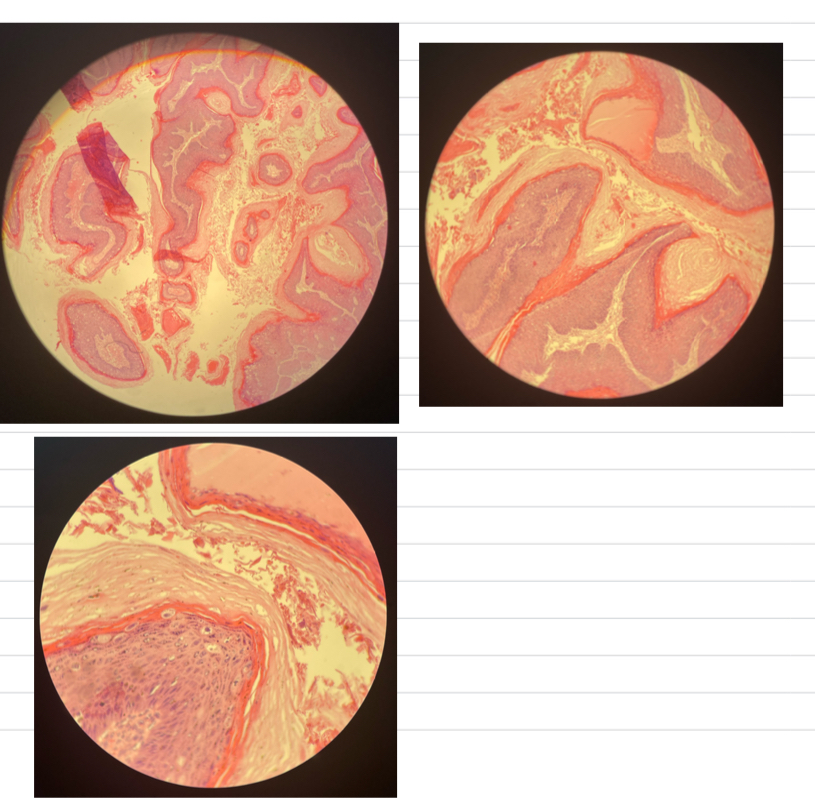

Papilloma => benign epithelial neoplasm

- CT core w/ neoplastic squamous epi

- papilloma is thick bc… acanthotic, hyperplasia, hyperkeratotic

Cornified layer is vacuolated

Squamous cell carcinoma => malignant epithelial neoplasm

- irregular masses + cords proliferating downwards

- ulcerations on surface

- keratin pearls

- coag. necrosis

- mitotic figures + neoplastic cells